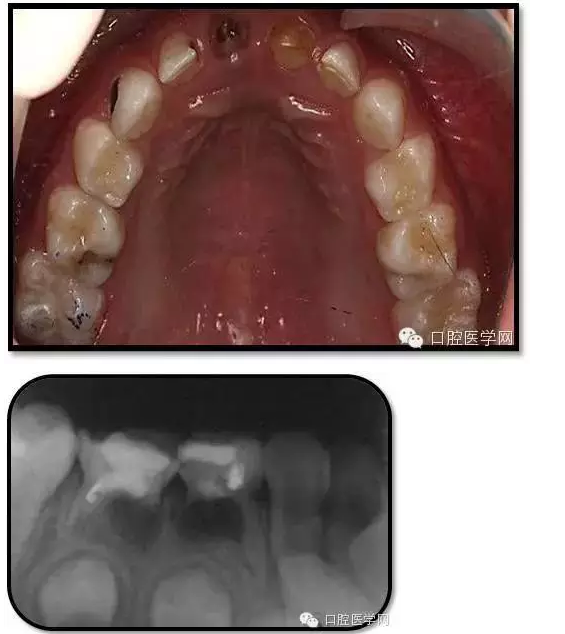

臨床檢查: 75OL齲洞, 舌側(cè)牙體完全劈裂斷端齊齦,探及大量軟化腐質(zhì)。頰側(cè)牙齦紅腫見瘺管,擠壓大量溢膿。叩(±),不松動。X線:75根管空虛,牙根吸收約1/2,根尖周及根分歧大面積透射影,35發(fā)育4期,骨硬板尚連續(xù);51殘根,唇側(cè)牙齦瘺管,叩(±),不松動。X線:51牙根吸收約1/2,根尖周低密度影。

85O、84DO充填體邊緣不密合,叩(±),不松動。84頰側(cè)牙齦略紅腫。X線:84遠中根及髓室底完全吸收,根分歧透射影,近中根內(nèi)側(cè)見外吸收,44上方骨硬板連續(xù)。85近中根完全吸收,髓室底吸收,根分岐透射影,遠中根管內(nèi)見根充影像。45發(fā)育4期,骨硬板連續(xù)。

QQ圖片20150728144435.png

QQ圖片20150728144451.png